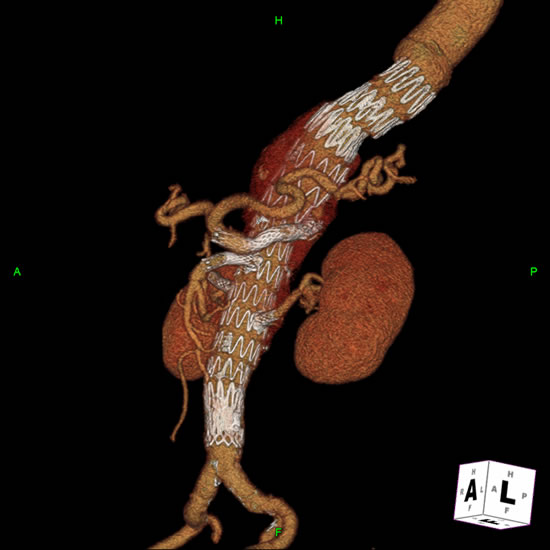

Stenting the branch vessels can now be performed via the previously placed access sheaths. Balloon expandable covered stents measuring 18-38mm in length and 6-9mm in diameter are deployed on 7mm x 4cm or 8mm x 4cm balloons mostly into the target vessel with approximately 3mm extending proximally into the aorta. The aortic portion of the stentgrafts should then be flared with a 10mm x 2cm balloon to rivet them in place within the main device (Figure 4). Further flaring with a larger compliant balloon (Coda) is selectively employed. Each stent should be completely deployed including the flaring process before proceeding to the subsequent one.

Some devices are designed with a combination of fenestrations and helical directional branches. These latter configurations are preloaded with wires to allow for easier access and are conjoined to the target branch vessels with self-expanding stentgrafts because their construct allows for a longer overlap and seal. Newer iterations of these devices have multiply preloaded branches and a unilateral delivery system.